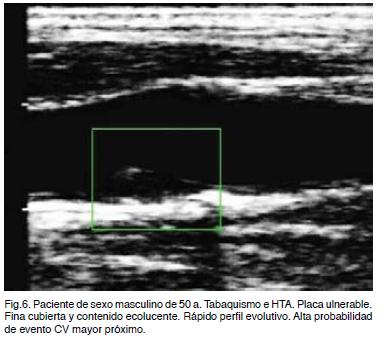

Placa vulnerable es aquella de rápida evolución y alta probabilidad de ruptura y trombosis configurando un estado inestable de alto riesgo y precursor de complicaciones. Su ruptura se produce por un proceso inflamatorio inmunomediado con liberación de enzimas proteolíticas y por factores hemodinámicos con un incremento anormal del shear stress oscilatorio. Son placas heterogéneas de cubierta fina, irregular, con alto contenido lipídico (ecolucente), nódulos cálcicos próximos a la cubierta de la placa, hemorragia intraplaca (ecolucente), remodelación expansiva y posible ulceración (Figura 6).